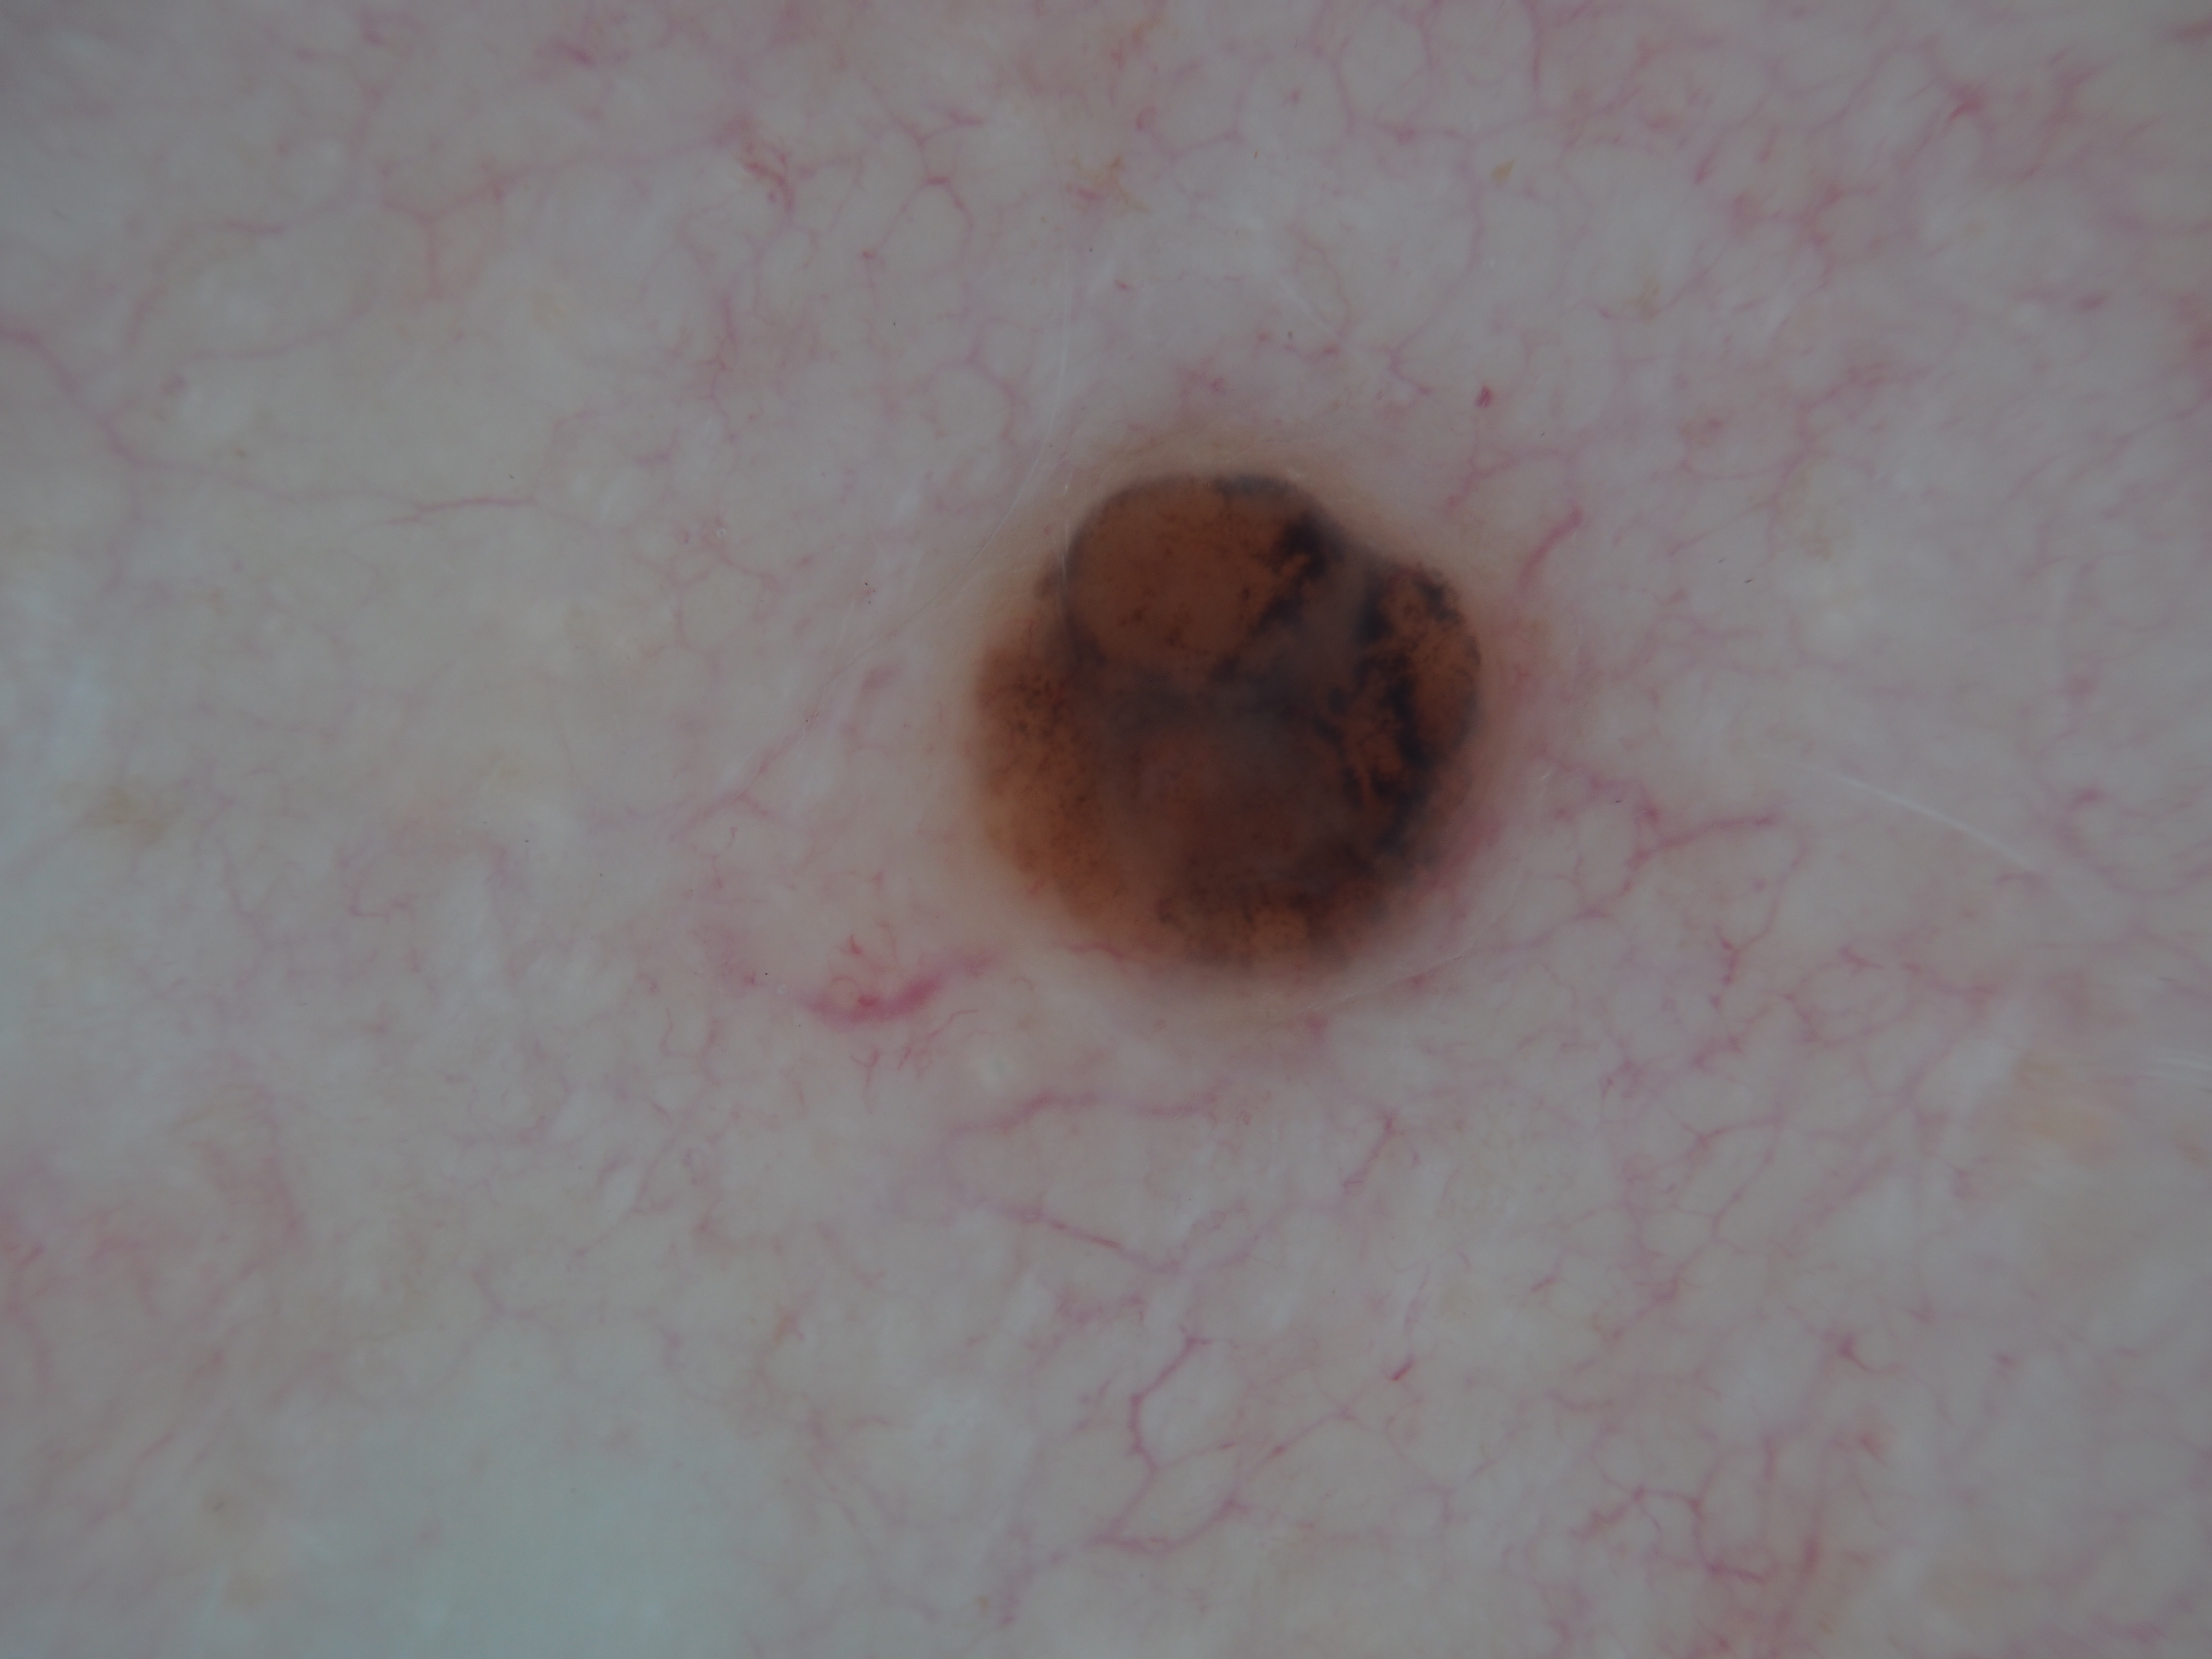

Site: Back

Diagnosis: Melanoma nodular

Pigmented lesion upper back

This lesion was noted during a routine skin examination in an elderly patient on immunosuppressives for an autoimmune disease.

The lesion was a 0.55 mm thick Clark level 3 nodular melanoma.